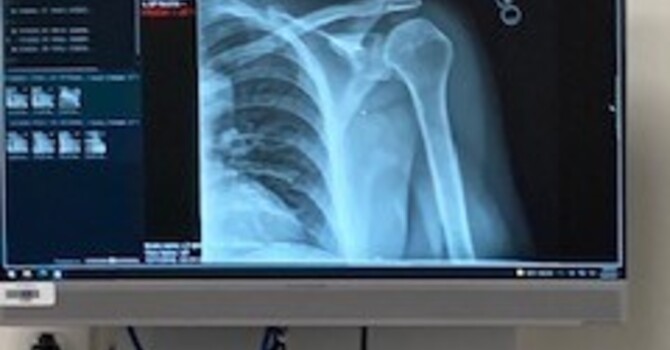

Poor spinal health can have significant negative effects on overall wellness. Conditions such as chronic back pain, herniated discs, and spinal misalignments can cause discomfort, reduce mobility, and impact daily life.In severe cases, spinal conditions can even lead to chronic disability.

Using ergonomic furniture, such as a chair or desk that is tailored to your body, can reduce the risk of developing spinal problems due to sitting for long periods. And if you do experience any spinal injuries or conditions, seeking prompt medical attention is critical.